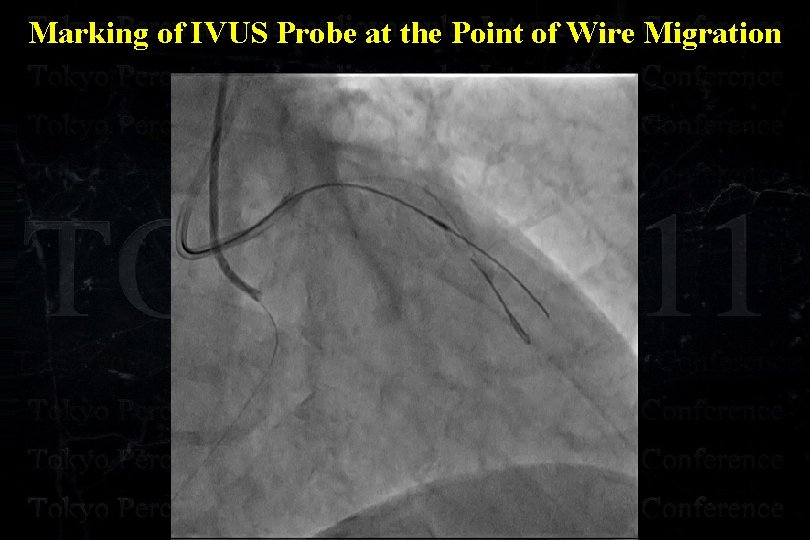

Marking of IVUS Probe at the Point of Wire Migration

Marking of IVUS Probe at the Point of Wire Migration

Marking of IVUS Probe at the Point of Wire Migration LAO cranial RAO caudal